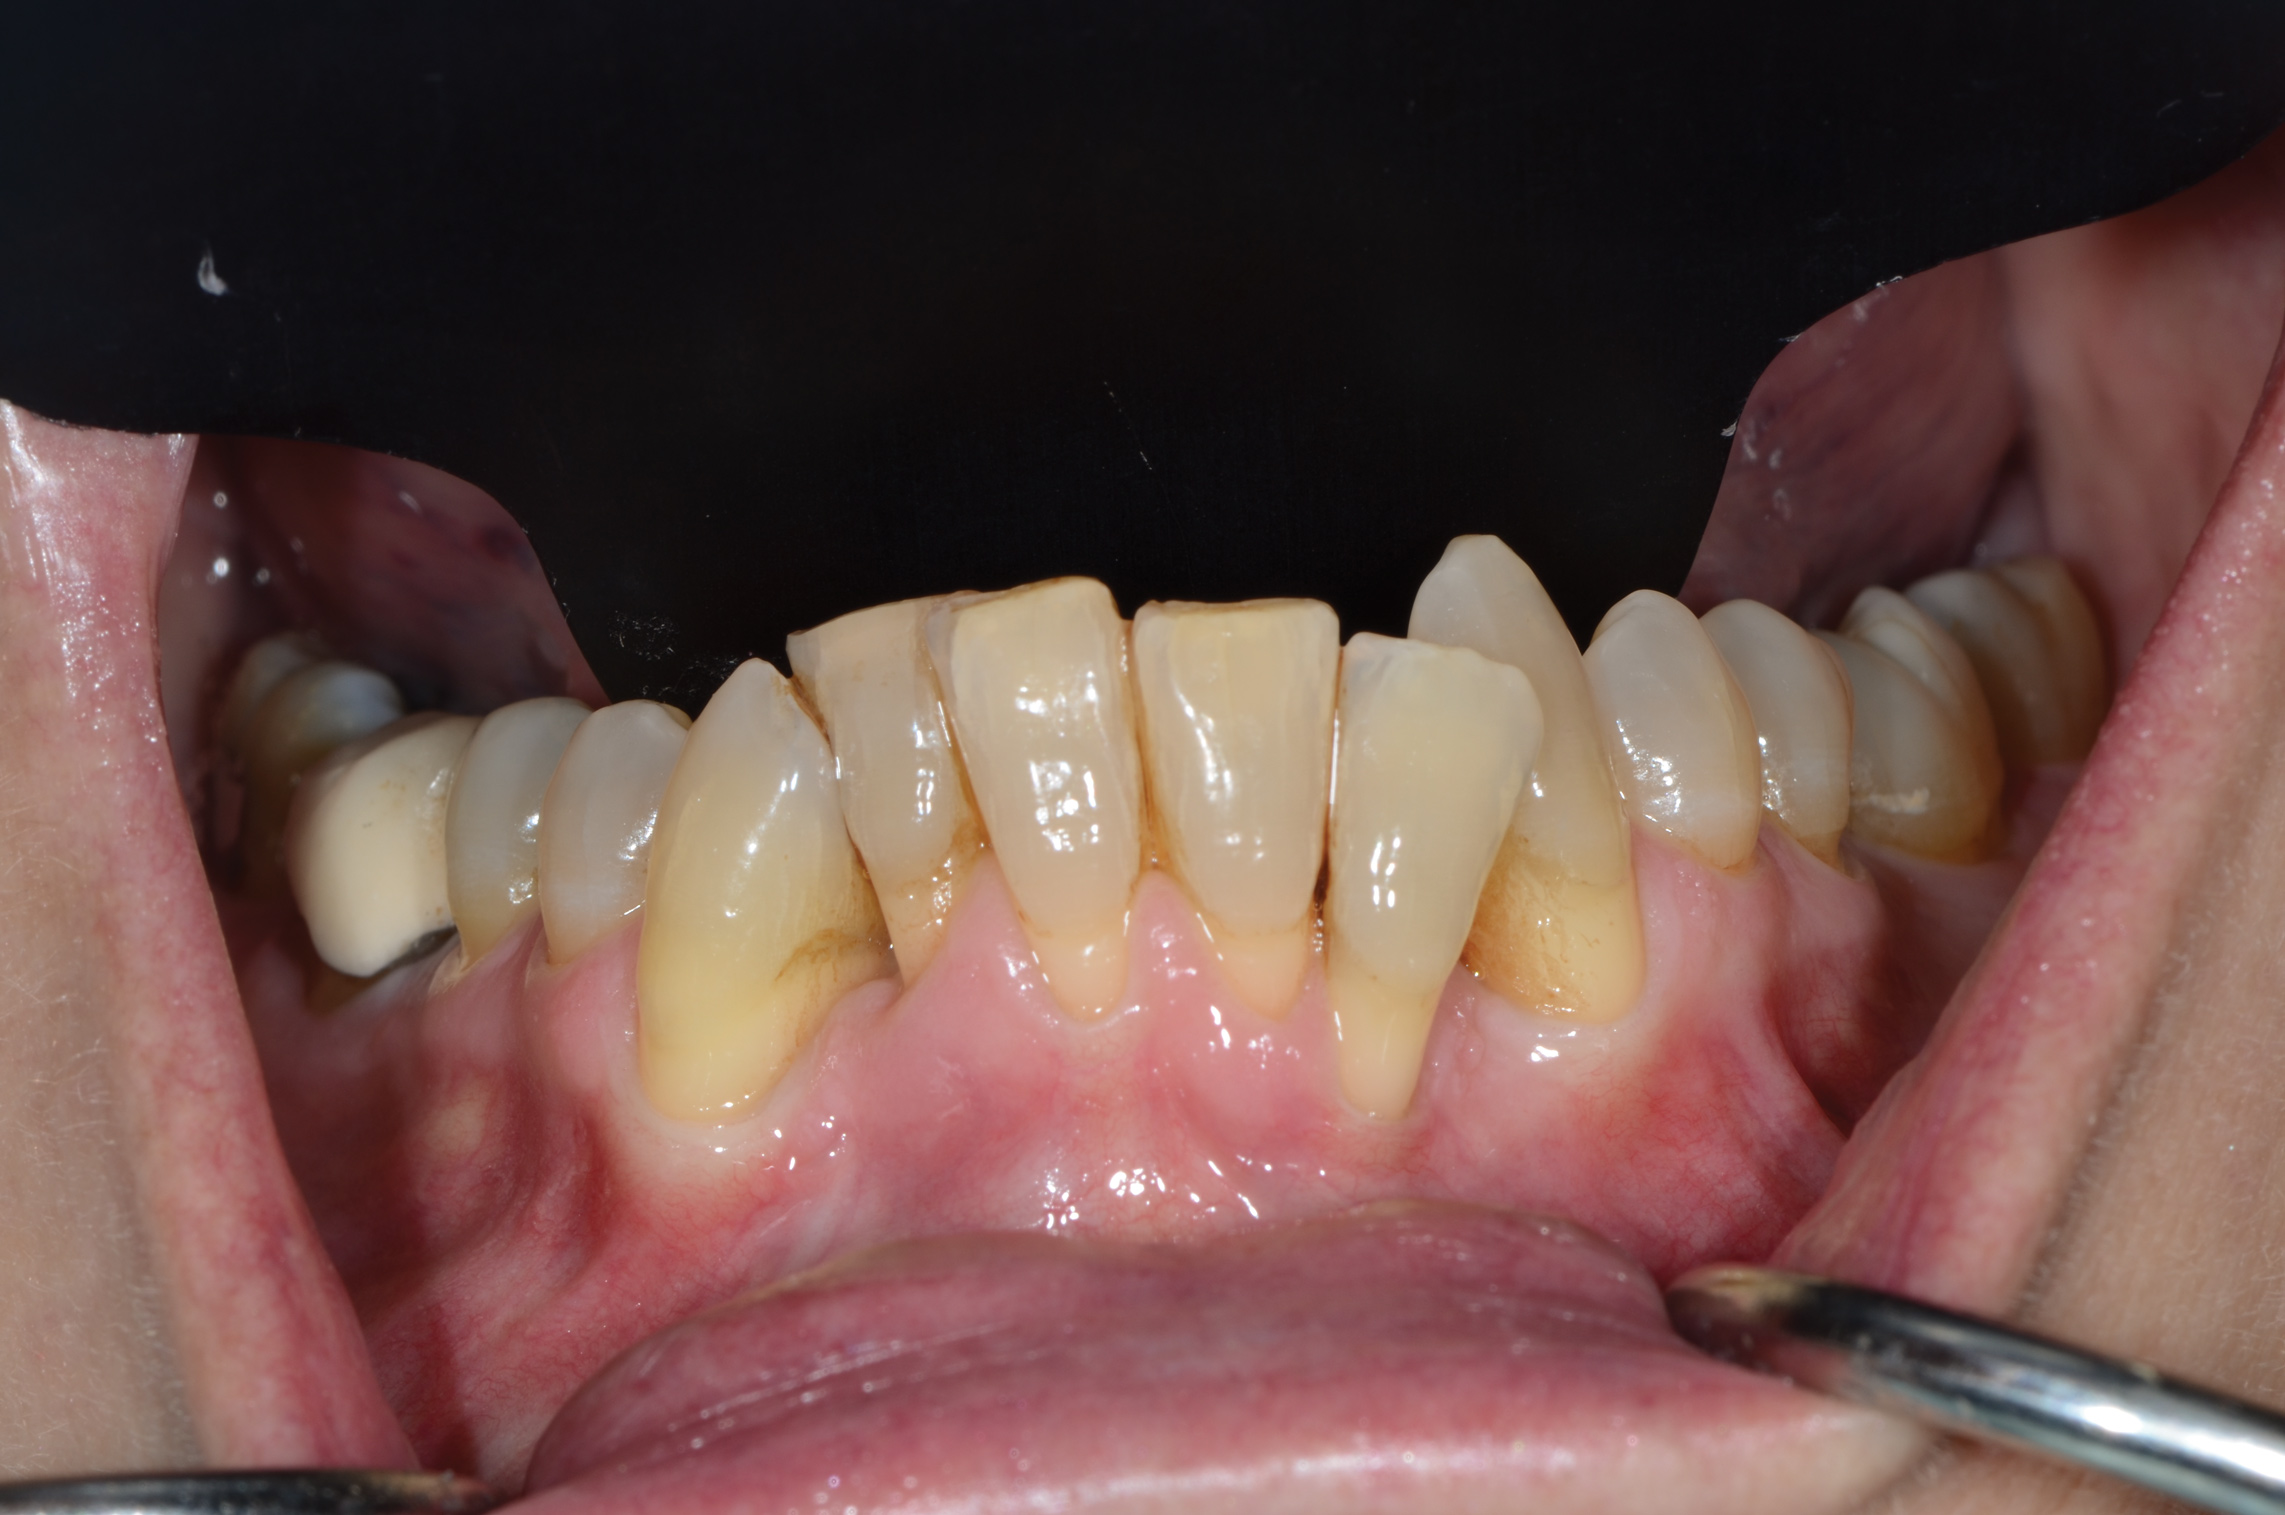

Fig 10. In this case a short vestibule was present prior to SFOT.

Figure 10